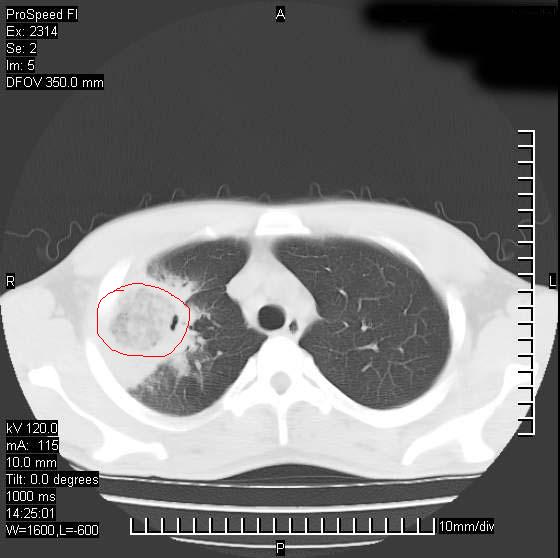

男性,再生障碍性贫血,入院前发热10天,最高40c,右侧胸痛,外院ct示右上,中肺边缘模糊的球性影(就是我现在图中标示的范围),考虑炎症,在我院使用头孢呋辛,洛美沙星10天,高烧消退,自感下午稍有发热,但今天ct示右上,中肺病灶明显扩大,还是考虑炎症,看其中的球型影是否霉菌感染??,是否能排除结核?

右肺中叶外侧段病变,上缘界限不清,下缘锐利,以段性发病为主,内见巨大空洞及空洞内容物,结合病史首先考虑:化脓性肺炎。不除外霉菌感染!

片状高密度影内见空洞影,内可见球形软组织密度影,并有新月征,考虑霉菌感染.